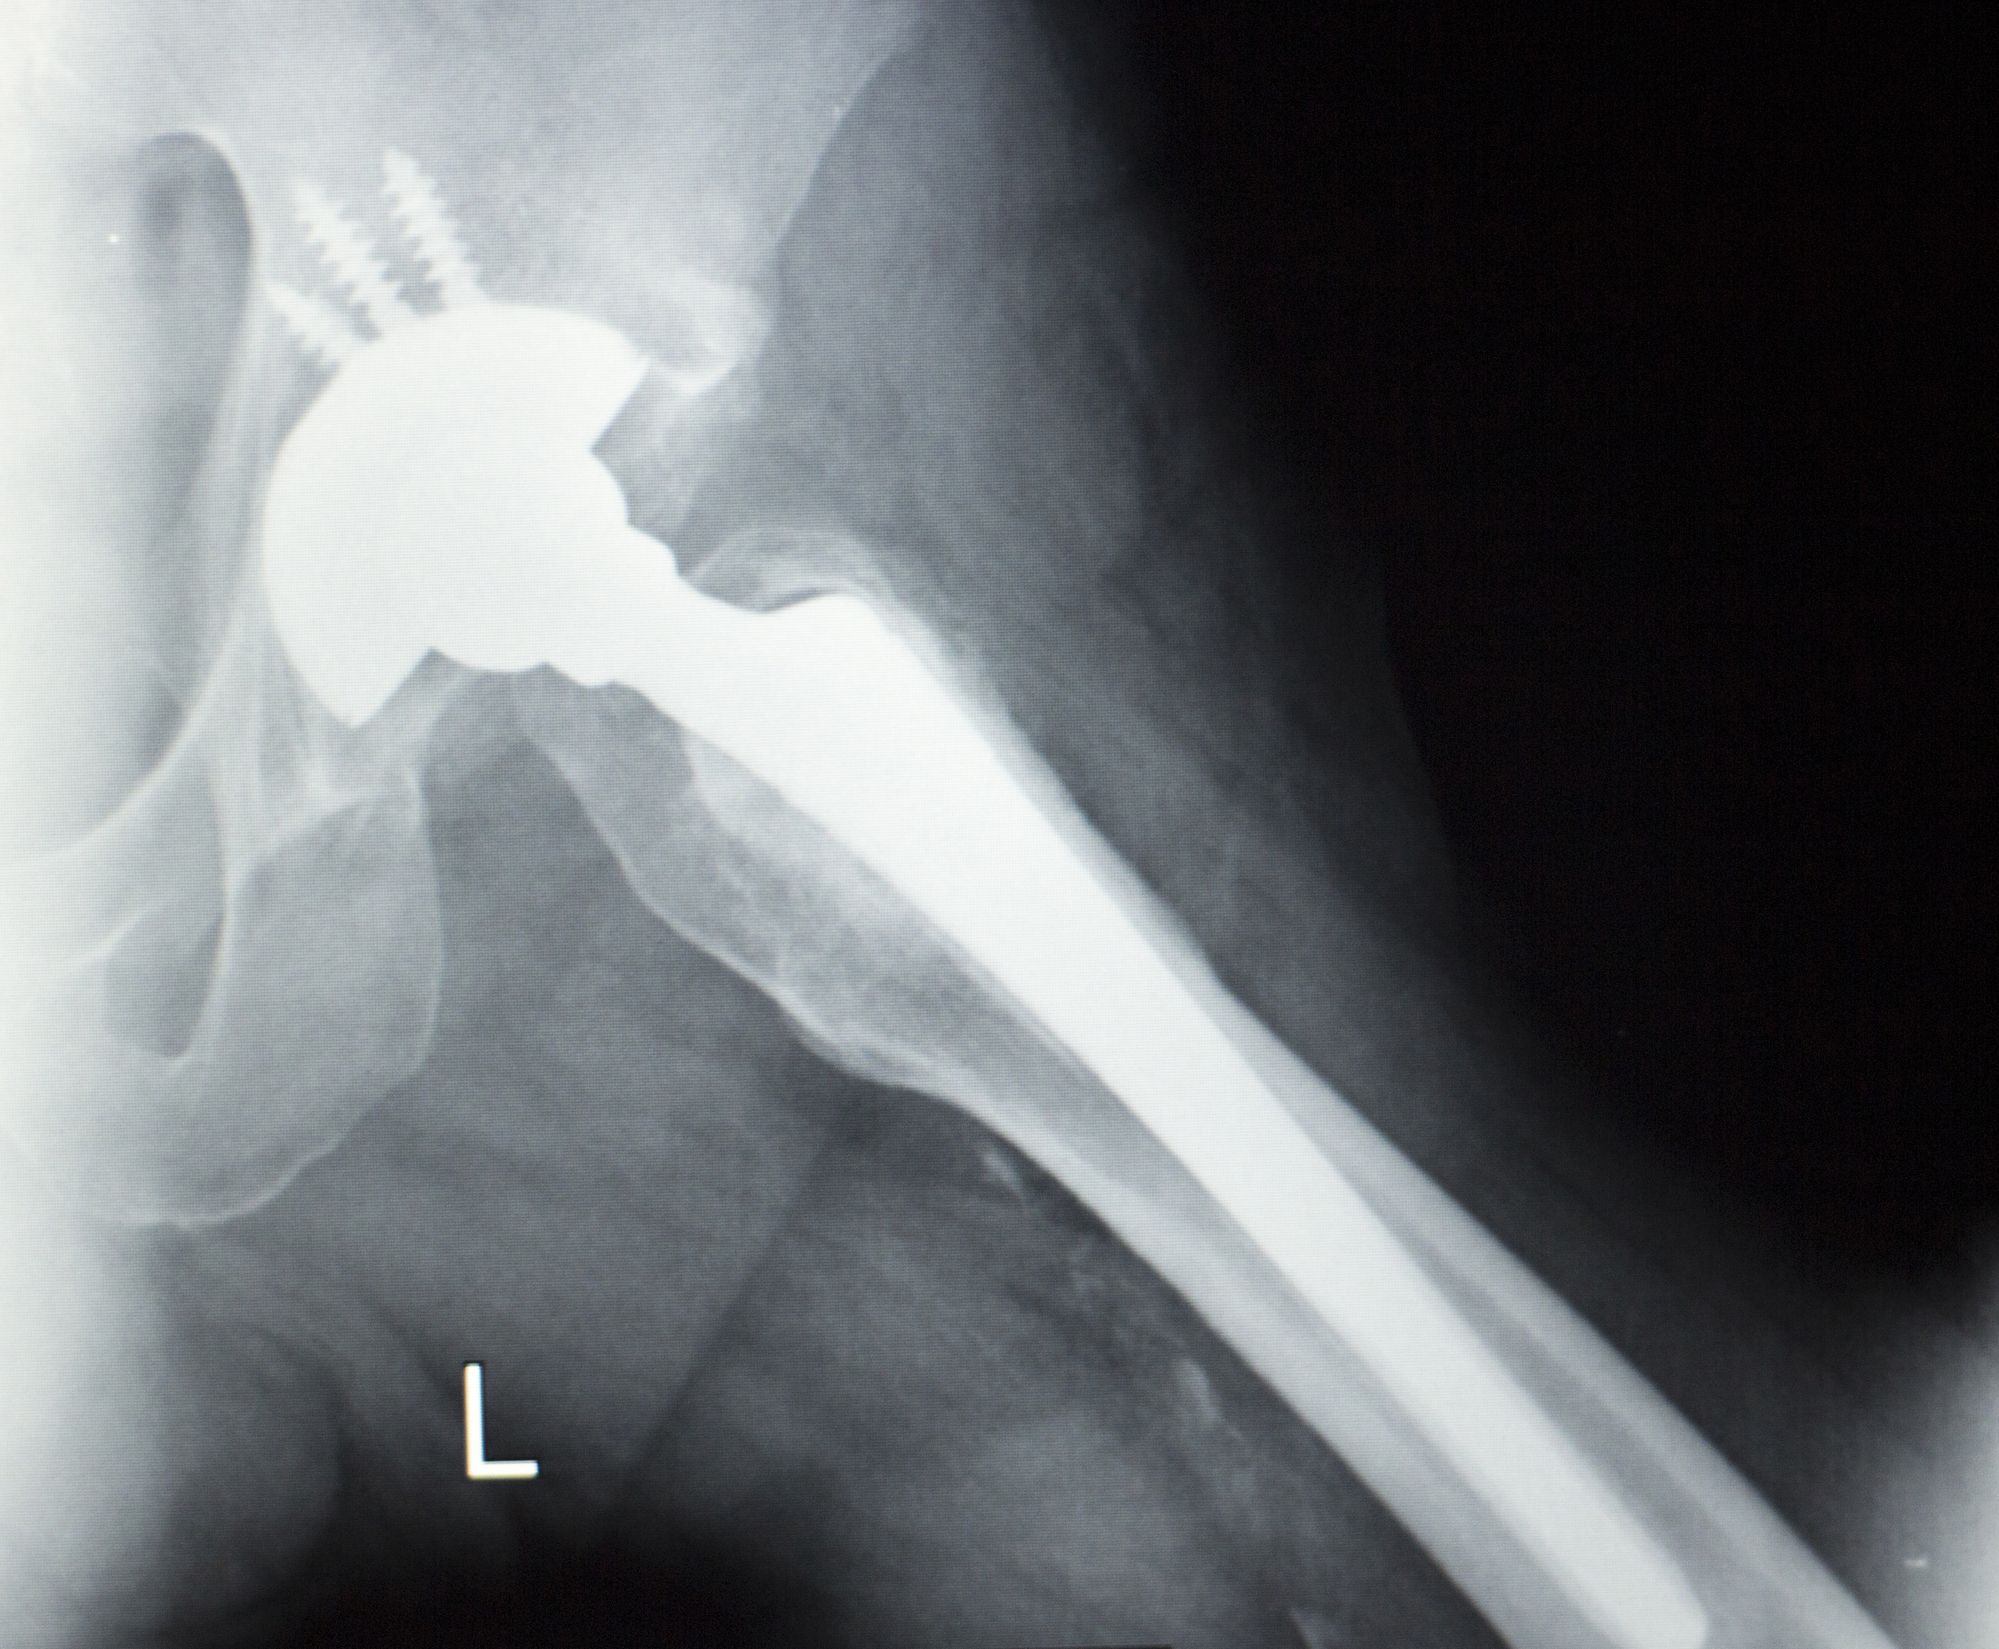

Stryker Hip Replacement Recall List . Please inform users of this urgent. Learn about the latest developments in stryker hip replacement lawsuits involving lfit v40, rejuvenate, abg ii and tritanium devices. Find out the causes, complications, settlements and lawsuits related to the recalls. Please contact your local sales office or your stryker sales representative directly for product replacement and inventory. On 10/15/2021, stryker issued urgent medical device recall notices to customers. Learn about the stryker hip implant recalls involving rejuvenate, abg ii, lfit v40 and accolade tmzf devices. The aaos device recall dashboard provides orthopaedic surgeons with timely recall information that will protect the health and well. Find out if you qualify to file a claim and what injuries are named in the lawsuits. The fda recommends not using or implanting the synovo total hip system, including resurfacing implants, after 2019 due to. Learn about the hip replacement lawsuits filed against stryker and other device makers for complications such as metal poisoning, infection, and nerve damage.

The fda recommends not using or implanting the synovo total hip system, including resurfacing implants, after 2019 due to. Learn about the stryker hip implant recalls involving rejuvenate, abg ii, lfit v40 and accolade tmzf devices. On 10/15/2021, stryker issued urgent medical device recall notices to customers. Find out if you qualify to file a claim and what injuries are named in the lawsuits. Learn about the latest developments in stryker hip replacement lawsuits involving lfit v40, rejuvenate, abg ii and tritanium devices. Please contact your local sales office or your stryker sales representative directly for product replacement and inventory. Please inform users of this urgent. The aaos device recall dashboard provides orthopaedic surgeons with timely recall information that will protect the health and well. Learn about the hip replacement lawsuits filed against stryker and other device makers for complications such as metal poisoning, infection, and nerve damage. Find out the causes, complications, settlements and lawsuits related to the recalls.

Stryker Hip Replacement Recall List Learn about the stryker hip implant recalls involving rejuvenate, abg ii, lfit v40 and accolade tmzf devices. Learn about the hip replacement lawsuits filed against stryker and other device makers for complications such as metal poisoning, infection, and nerve damage. Please inform users of this urgent. Find out the causes, complications, settlements and lawsuits related to the recalls. On 10/15/2021, stryker issued urgent medical device recall notices to customers. The aaos device recall dashboard provides orthopaedic surgeons with timely recall information that will protect the health and well. Learn about the stryker hip implant recalls involving rejuvenate, abg ii, lfit v40 and accolade tmzf devices. Find out if you qualify to file a claim and what injuries are named in the lawsuits. Please contact your local sales office or your stryker sales representative directly for product replacement and inventory. The fda recommends not using or implanting the synovo total hip system, including resurfacing implants, after 2019 due to. Learn about the latest developments in stryker hip replacement lawsuits involving lfit v40, rejuvenate, abg ii and tritanium devices.